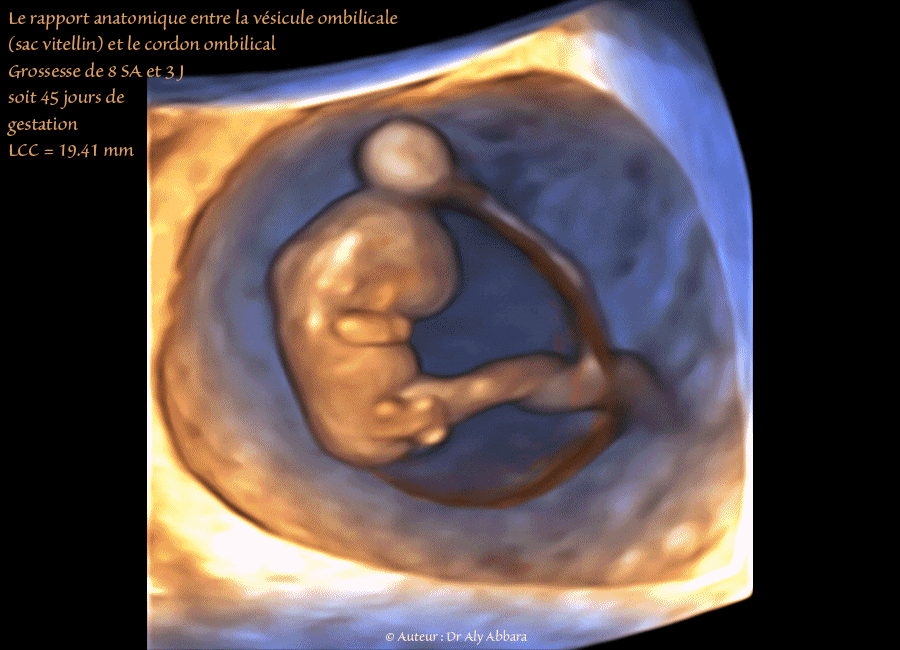

Embryon âgé de 45 jours de gestation (8 SA + 3 jours) - Vésicule ombilicale - مضغة بعمر 45 يوماً  - الحويصل السري

• Images échographiques montrant un embryon âgé de 45 jours de gestation (soit 8 semaines d'aménorrhée et 3 jours) et mettant en évidence les rapports anatomiques de la vésicule ombilicale (sac vitellin) avec les autres éléments composant la grossesse :

• La vésicule ombilicale qui évolue dans l'espace cœlomique externe ou la cavité choriale (l'espace situé entre le chorion et l'amnios et qui disparaîtra plus tard, vers 12 - 13 SA, quand l'amnios rejoint le chorion).

• Le micro-cordon vitellin ou le pédicule vitellin grêle (contenant un micro-vaisseau) qui relie la vésicule ombilicale au cordon ombilical embryonnaire, souvent au niveau du pilier de fixation du cordon ombilical au chorion, mais dans le cas présenté dans cet article, la zone de ralliement se situe directement sur le cordon ombilical embryonnaire, à distance de ce pilier de fixation.

• Le pédicule vitellin grêle parcourt la surface exterieure de la cavité amniotique (la surface extérieure de l'amnios ou la membrane amniotique) avant son ralliement au cordon ombilcal.

°A l'intérieure de la cavité cœlomique externe (cavité choriale) on retrouve le sac amniotique limité par l'amnios et contenant

“ un embryon de 19,41 mm de longueur crânio-caudale avec son cordon ombilical.

On distingue nettement les deux pôles embryonnaires : le pôle céphalique et le pôle caudal ; le tronc et les ébauches des 4 membres comportant chacun trois segments ”